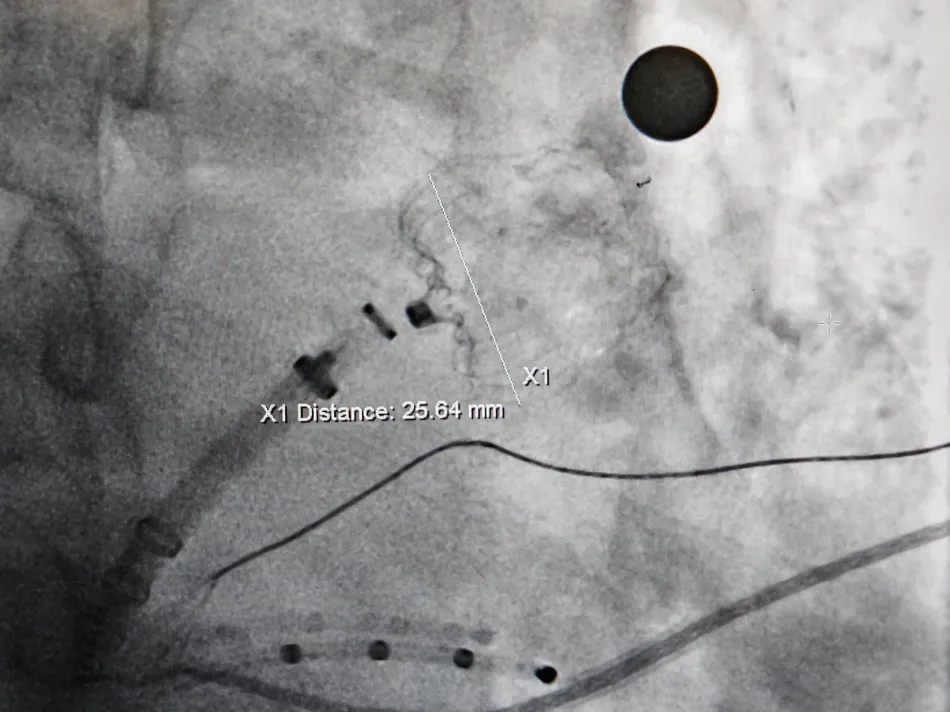

测量压缩比

压缩比10%

造影评估后封堵器释放

Lefort封堵器评估符合PASS原则,释放封堵器,封堵器位置稳定且未见残余漏

术前结合CT以及术中造影评估左心耳开口23.27mm,深度22.45mm,心耳内部空间较大,且患者全身情况良好,可较配合局部麻醉手术,采用极简式封堵术安全可行。术中考虑心耳开口和深度充足,可利用心耳空间进行退鞘释放封堵器,使封堵器完全封堵左心耳。术中采用半回收方式调整封堵器在心耳内的位置形态,确保封堵器放置位置合适,且牵拉稳固,术后封堵器形态完整,未见残余漏。本病例展开后即刻造影,平口封堵,上下缘不留残腔。封堵器压缩比为10%,压缩合适,术中符合PASS原则,释放封堵器,术后封堵器稳固锚定在心耳壁,封堵器与心耳紧密贴合,无过度扩张风险,显著提升封堵完整性。